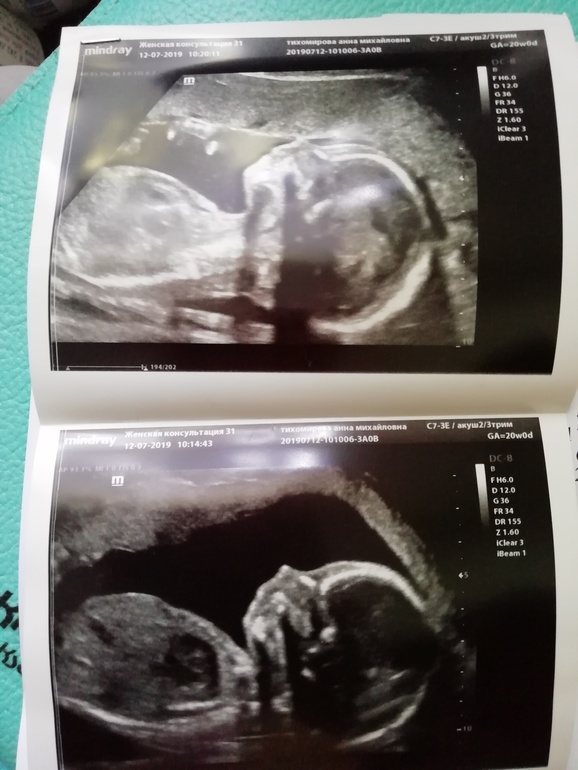

💙💙💙 Ну и сам малыш